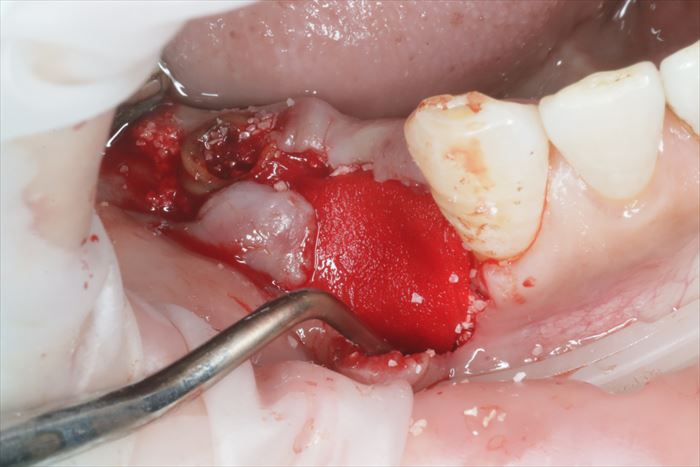

コラーゲン膜(コラーゲンメンブレン)を骨欠損の外側に挿入して囲いを作り、骨移植材を骨欠損部位に填入しました。

コラーゲンメンブレンで表面を保護して軟組織の侵入を防ぎます。